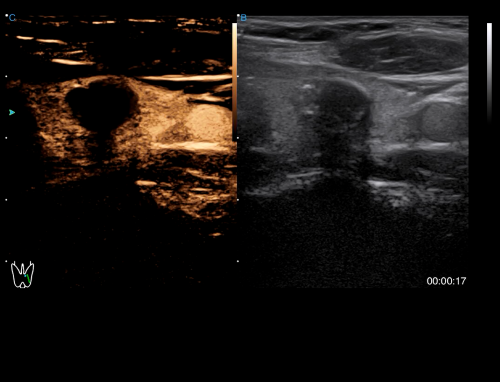

Radiology

· CHI visualizes blood perfusion status in real-time with high image contrast to detect micro lesions and outline tumor.

· HRI QA assesses hepatic steatosis by quantitative results with multiple sampling points available.

· Strain Elastography assists in analyzing tissue stiffness to detect potential abnormalities.